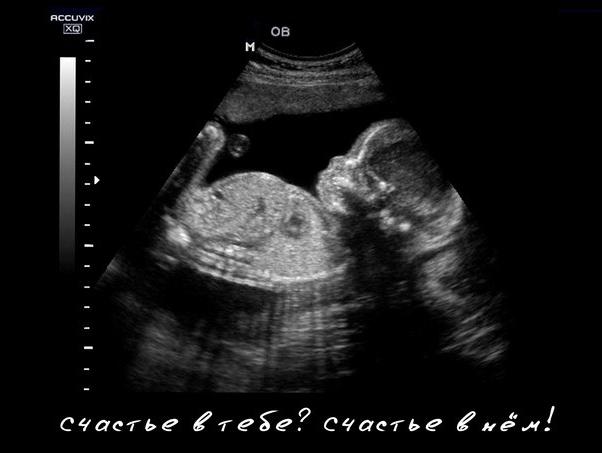

Моё негодование и предостережение! Была на скрининге в кардио, отправили делать узи(кот.в переходе) делает всегда мужик(слов к нему больше нет!) во первых делает с малым кол-м геля, живот неприятно, во вторых так быстро, дольше раскладываешься, а в третьих и самое главное. Насмотрел такую х...что ребёнок у меня отстаёт в физическом развитии(это мне потом уже расшифровали его записи) хотя я спросила все ли хорошо с ребёнком? ДА ответил он. Пришла с результатами от него, меня срочно на повторное узи, смотрели 20 минут, все мерили, итог как могли вам такое сказать, все размеры тютелька в тютельку и щекастый ребёнок!!)) я счастлива, мужик-узист не профессионал!!!! Будьте аккуратнее с его результатами!!!! Всем добра🌺

А мне он понравился. Четкий такой мужик. Все по делу. Хорошо, внимательно посмотрел. Правда нашел гольфный мяч у малышки в сердечеке, на экране показал что это из себя представляет и даже успокоил, сказав, что это просто особенность развития и это должно пройти. В конце монитор ко мне повернул и ляльку дал рассмотреть внимательно. Была на скрининге в начале марта.